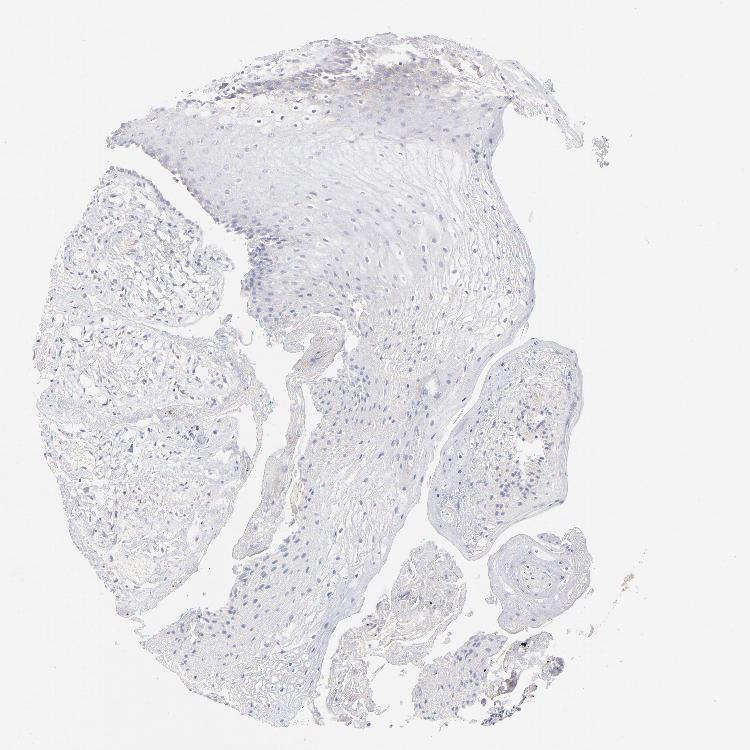

TISSUE PRIMARY DATA ORAL MUCOSA Show tissue menu

ORAL MUCOSA - Antibody stainingi

Antibody staining in the annotated cell types in the current human tissue is reported as not detected, low, medium, or high, based on conventional immunohistochemistry profiling in selected tissues. This score is based on the combination of the staining intensity and fraction of stained cells.

Each image is clickable and will lead to virtual microscopy that enables deeper exploration of all samples and also displays staining intensity scores, fraction scores and subcellular localization as well as patient and tissue information for each sample.

Antibody HPA003029

Squamous epithelial cells Not detected